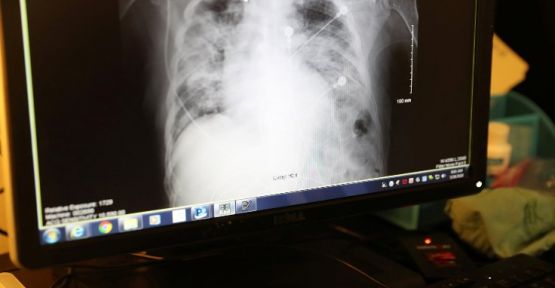

Devlet Nükleer Enerji Şirketi Rosatom’un, korona virüsüne karşı yeni bir tedavi geliştirdiği belirtildi. 'Parlayan gaz' adı verilen yöntemde, akciğerler ultraviyole ışınlarıyla dezenfekte ediliyor.

Rusya Devlet Nükleer Enerji Şirketi Rosatom’un önde gelen bilim merkezlerinden biri olan Leypunsk Fizik ve Enerji Enstitüsü’nden (FEI) uzmanların, korona virüsünün tedavisinde yeni bir yöntem geliştirdiği belirtiliyor. Buna göre, söz konusu yöntemde akciğerler ultraviyole ışınlarıyla dezenfekte ediliyor.